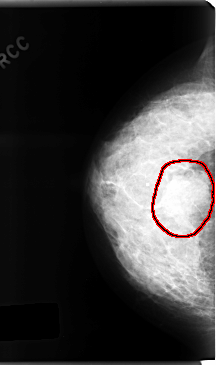

FILE: C_0166_1.RIGHT_CC.OVERLAY

TOTAL_ABNORMALITIES 1

ABNORMALITY 1

LESION_TYPE MASS SHAPE OVAL MARGINS SPICULATED

ASSESSMENT 5

SUBTLETY 5

PATHOLOGY MALIGNANT

TOTAL_OUTLINES 1

BOUNDARY